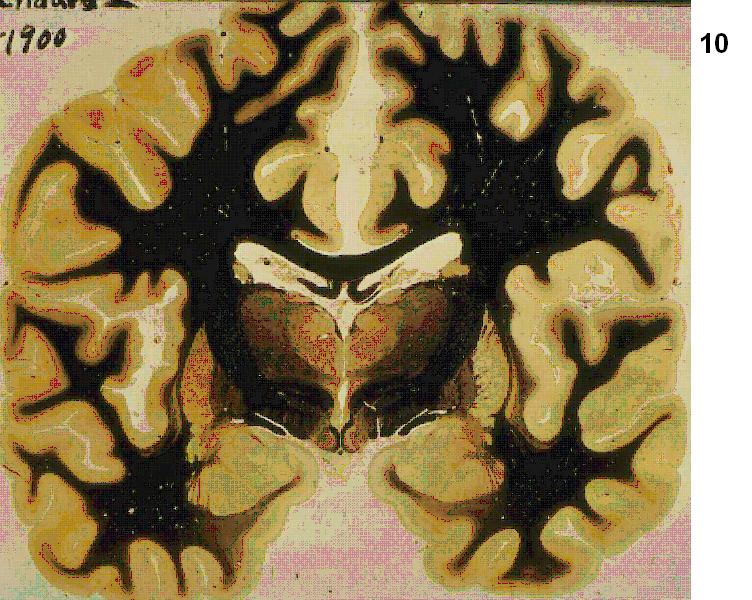

Figure 4 Figure 5 Figure 6 Figure 7 Figure 8 Figure 9 Figure 10 Figure 11

Figure 12 Figure 13 Figure 14 Figure 15 Figure 16 Figure 17